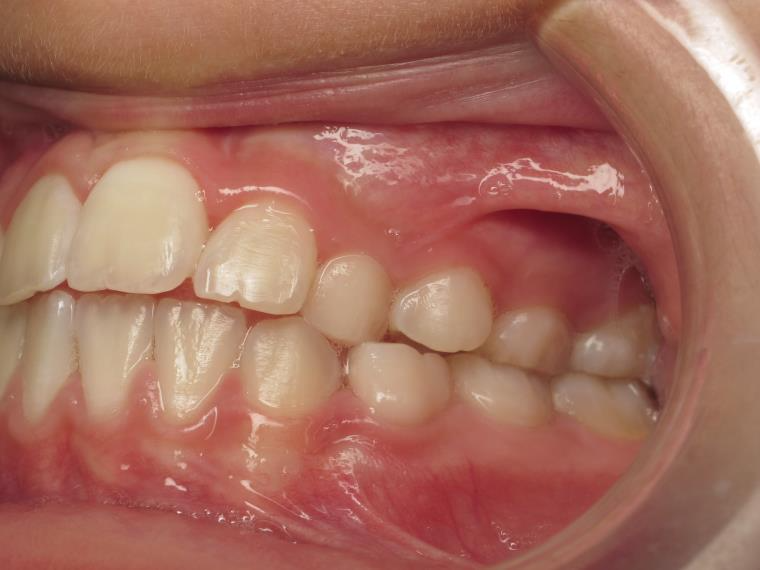

9. inversé gauche 6 ans

inversion des dents posterieur cote gauche

appareillage mobile pendant 9 mois